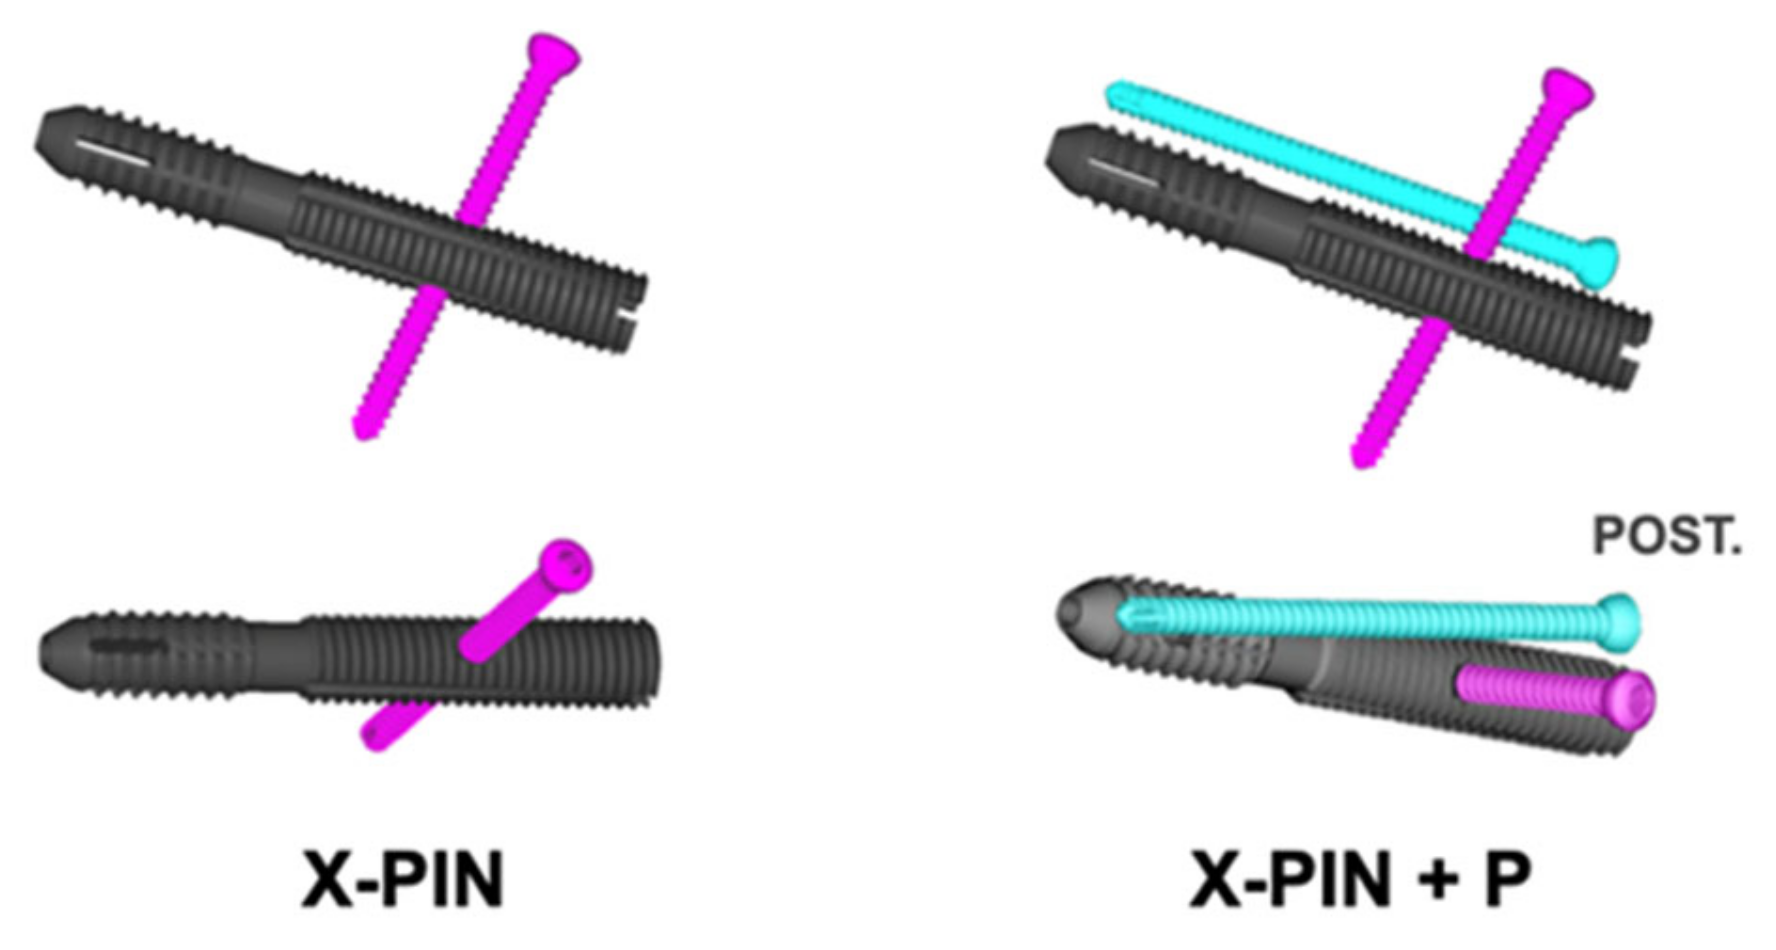

2. Materials and Methods

3. Results

4. Discussion